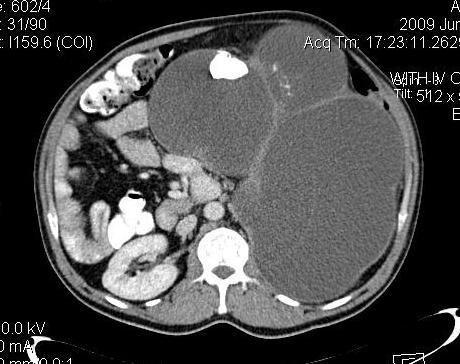

We report a case of primary mucinous cystadenocarcinoma of renal pelvis which radiologically resembled large multicystic mass in 45 years old man.

The patient referred to our center with loin pain and progressive abdominal distention from 4 years ago. In the previous published literature, four cases of mucinous cystadenocarcinoma of renal origin have been published. Abdominal CT showed complete replacement of left kidney by a large multiloculated cystic mass accompanied with multiple large nephrolithiasis. Nephrectomy was performed and histopathology revealed covering of epithelium of renal pelvis by columnar epithelium and scattered goblet cells and mucous gland.